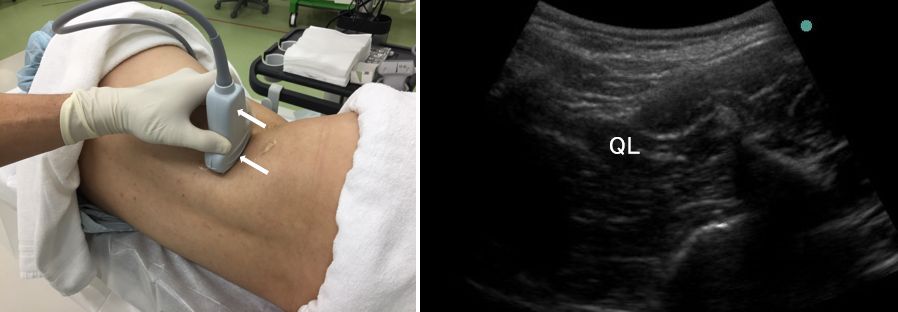

(2)腰方形筋が同定できたら、プローブを頭側へ移動し

腰方形筋の形が変化していく様子を観察します。

扁平になりましたね。

(3)ここで、腰方形筋を画像の中心に据えながら、プローブを回転させましょう。

これまでは、腰方形筋の横断面をみていましたが、縦断面がでるようにします。

うまく回転させないと、腰方形筋を見失ってしまうので気を付けてください。